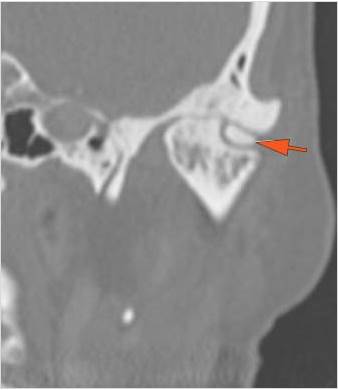

There is condylar fracture either within or outside of the joint capsule, or with or without involvement of the articular surface of the condylar head.

There is evidence of radiodense intra-articular osteochondral fragments.